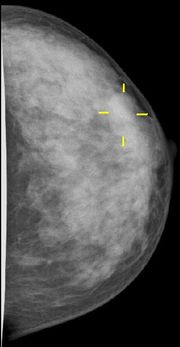

Ein Karzinom in der Mammographie

Die Röntgen-Mammographie ist einer S3-Leitlinie (Medizinische Leitlinie der höchsten Qualitätsstufe) zufolge bis jetzt das einzige Verfahren, dessen Eignung zur Erkennung früher Karzinome und Karzinomvorstufen allgemein anerkannt ist [36]. Die Mamma-Kernspintomographie ist möglicherweise überlegen, jedoch für ein Massenscreening zu teuer [37]. In Deutschland wird deshalb ein qualitätsgesichertes Mammographie-Screening-Programm auf der Grundlage der „Europäischen Leitlinien für die Qualitätssicherung des Mammographie-Screenings“ für Frauen von 50–69 Jahren aufgebaut. Insgesamt 94 dieser Einheiten sind bis Ende 2008 in ganz Deutschland geplant. Etwa 84 Regionen bieten das Mammographie-Screening bereits für die Zielgruppe, Frauen zwischen 50 und 69 Jahren, an (Stand Januar 2008) [38] In den USA gibt es die Empfehlung, das Mammographiescreening bereits mit 40 Jahren zu beginnen[34].

Die Mammographie ist bei Frauen mit dichtem Drüsengewebe in ihrer Aussagekraft begrenzt. Bei extrem dichtem Gewebe werden etwa 50 % der Brusttumoren mammographisch nicht entdeckt. Dies betrifft in erster Linie jüngere Frauen. Frauen mit dichtem Gewebe im Mammogramm wird daher der Einsatz eines zweiten Untersuchungsverfahrens (in der Regel Sonographie, im Einzelfall auch Kernspin-Mammographie) empfohlen.